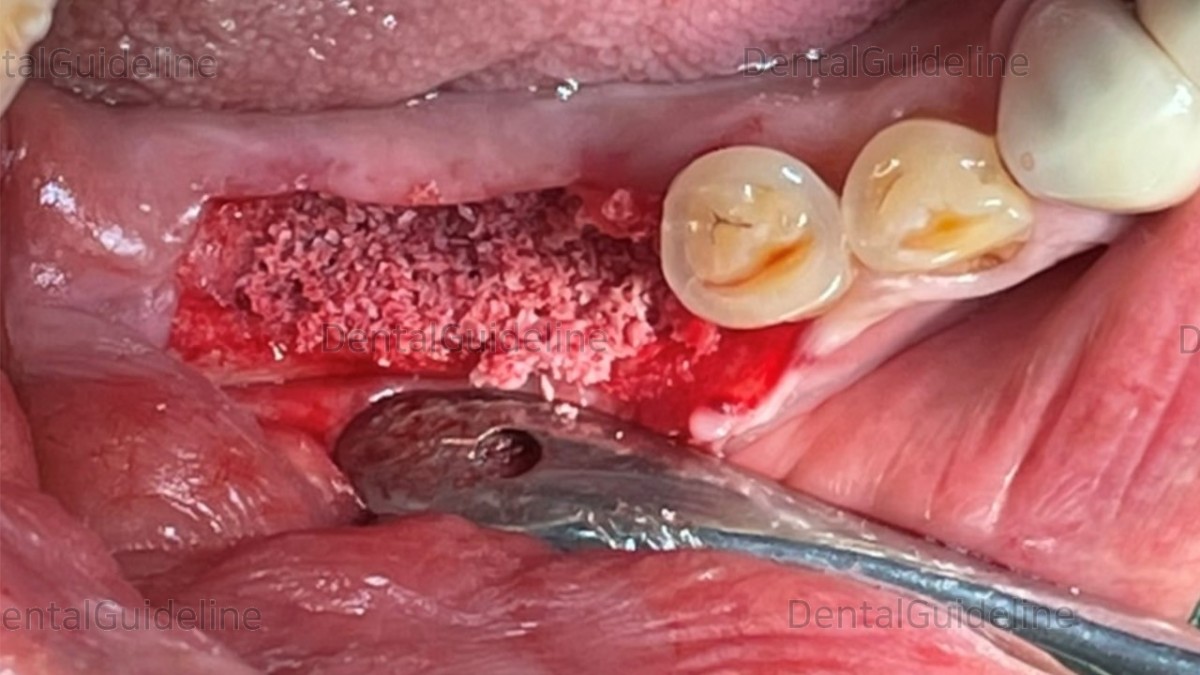

Additive GBR was performed.

collagen membrane